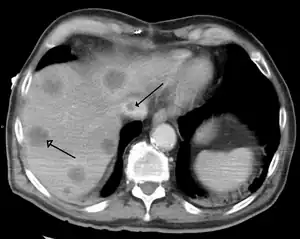

A síndrome de Budd-Chiari é mais habitualmente diagnosticada usando-se ultrassonografia abdominal e tomografia computadorizada helicoidal/multislice do abdome. O ultrassom pode mostrar a obliteração das veias hepáticas, trombose ou estenose, grandes vasos colaterais ou um cordão hiperecoico substituindo uma veia normal. A tomografia mostra a presença do trombo no interior dos vasos e/ou a ausência de fluxo vascular.